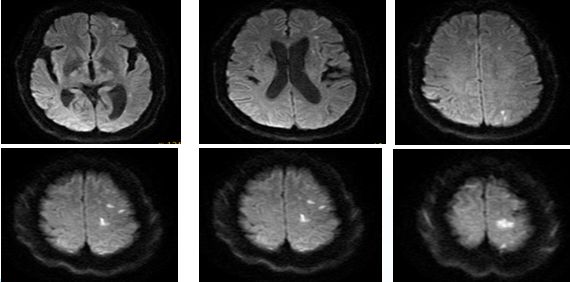

16:00:患者查颅脑磁共振

16:10:左侧额叶、顶叶、侧脑室旁多发急性脑梗死;多发缺血、梗死、软化灶;

左侧颈内动脉闭塞,具体原因不详,狭窄?夹层?

17:20颅脑CT排除出血

术后24小时复查,比入院后症状加重前稍加重